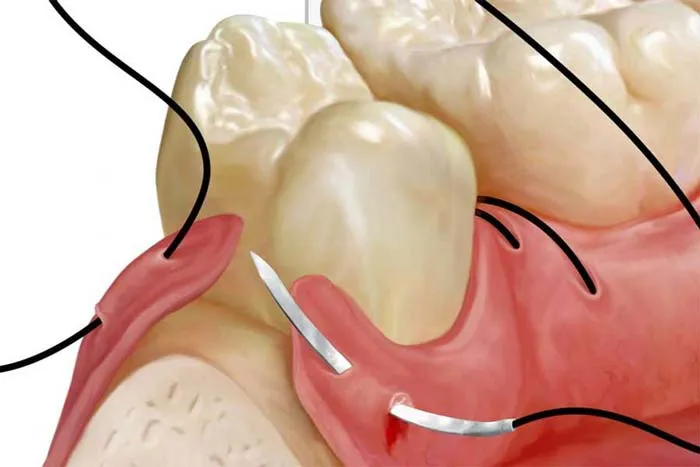

اهمیت نخ بخیه ایمپلنت در جراحی

بخیهها در دهان فقط برای بستن زخم نیستند؛ آنها مانند یک پانسمان هوشمند عمل میکنند که لبههای لثه را در کنار هم نگه میدارد تا لخته خون پایدار بماند و استخوان زیرین برای جوش خوردن با پایه ایمپلنت آماده شود.

انواع بخیه در جراحی ایمپلنت

| ویژگی | بخیه جذبی (Vycryl/Gut) | بخیه غیرجذبی (Silk/Nylon) |

|---|---|---|

| نیاز به کشیدن | ندارد (خودبهخود جذب میشود) | دارد (بعد از ۷-۱۴ روز) |

| میزان التهاب | کمی بیشتر (به دلیل واکنش شیمیایی جذب) | بسیار کم |

| راحتی بیمار | بالا (نیاز به جلسه دوم ندارد) | متوسط (استرس کشیدن بخیه) |

| کاربرد اصلی | جراحیهای داخلی و لایههای زیرین | جراحیهای وسیع و بازسازی استخوان |